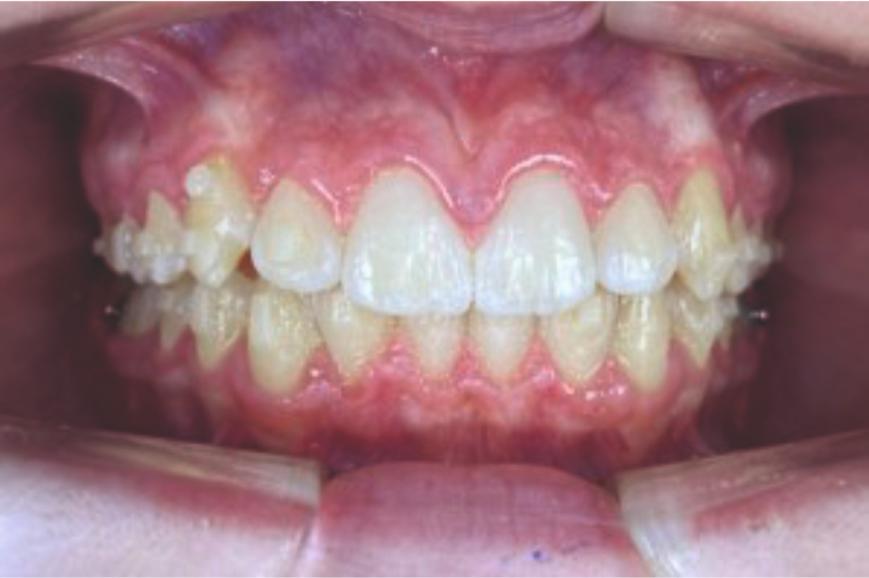

Chief complaint: We present the case of a 12-year-old female patient who came for an orthodontic evaluation, motivated by a family history of treatment. Clinical and radiographic analysis revealed a skeletal Class II malocclusion with molar and canine relationships also in Class II, moderate crowding in both arches, a deviation of the dental midline, and ectopic eruption of tooth 13. No functional issues with breathing or swallowing were observed, and oral health was generally good. A slight mandibular retrusion was noted in the soft tissue profile. A treatment plan was proposed using the Angel Aligner Pro system, aiming to correct dental misalignments and improve facial harmony through a minimally invasive, growth-adapted approach.

Clinical examination and diagnosis

- Woman ; 12/3 years

- Skeletal Class II

- Molar and canine Class II

- Upper and lower dentoalveolar compression

- Increased overjet and overbite

- Upper midline deviated 0,5 mm to the right

- Moderate upper and lower crowding

We approached the case by combining upper distalization using the A8 protocol with an asymmetric virtual jump. In this way, we solved the crowding without proinclining the incisors and improved the anteroposterior relationship through the use of elastics. In the lower arch, we carry out a development of the posterior sectors prior to the resolution of the crowding, in order to avoid roundtripping and excessive IPR of the incisors. To achieve an effective extrusion and distalization of 13, we combine the use of direct bonding button on vestibular of 13, with angelButton elastics mesial and distal to the canine. These mechanics help to ensure that the extrusion is real and that the aligner always remains adapted.

In the upper arch, the main goal will be to correct the Class II malocclusion by distalizing the upper posterior teeth in order to resolve crowding without proinclining the incisors. This movement will be accompanied by an asymmetric “bite jump” of 1 mm, which will help improve the skeletal Class II discrepancy, promoting mandibular projection, especially considering that the patient is still in the growth phase. Additionally, bilateral and symmetric expansion will be planned until a torque of 0° is achieved, allowing for proper transverse alignment and greater stability of the final result. Lingual button cutouts will be placed on teeth 14 and 24 to facilitate the required movements. To optimize control and retention, vertical mesial beveled attachments, as large as possible, will be placed on the premolars and molars, as well as on teeth 12 and 22, reinforcing the mechanics in the anterior sector. The inclination of the central incisors 11 and 21 will be corrected according to the visual reference provided in the clinical image. Furthermore, it will be necessary to center the upper midline by shifting it 0.5 mm to the left to achieve greater aesthetic symmetry. As for the lower arch, treatment will begin with a phase of expansion and derotation of the posterior teeth, which will set the stage for subsequent movements in the anterior sector. Once this goal is achieved, alignment of the teeth from canine to canine will proceed, aiming to minimize anterior interproximal reduction (IPR) and avoid unnecessary round- tripping movements of the incisors. Vestibular button cutouts will be made on teeth 36 and 46, while teeth 37 and 47 will have horizontal attachments that will serve as anchorage to ensure stability during treatment.